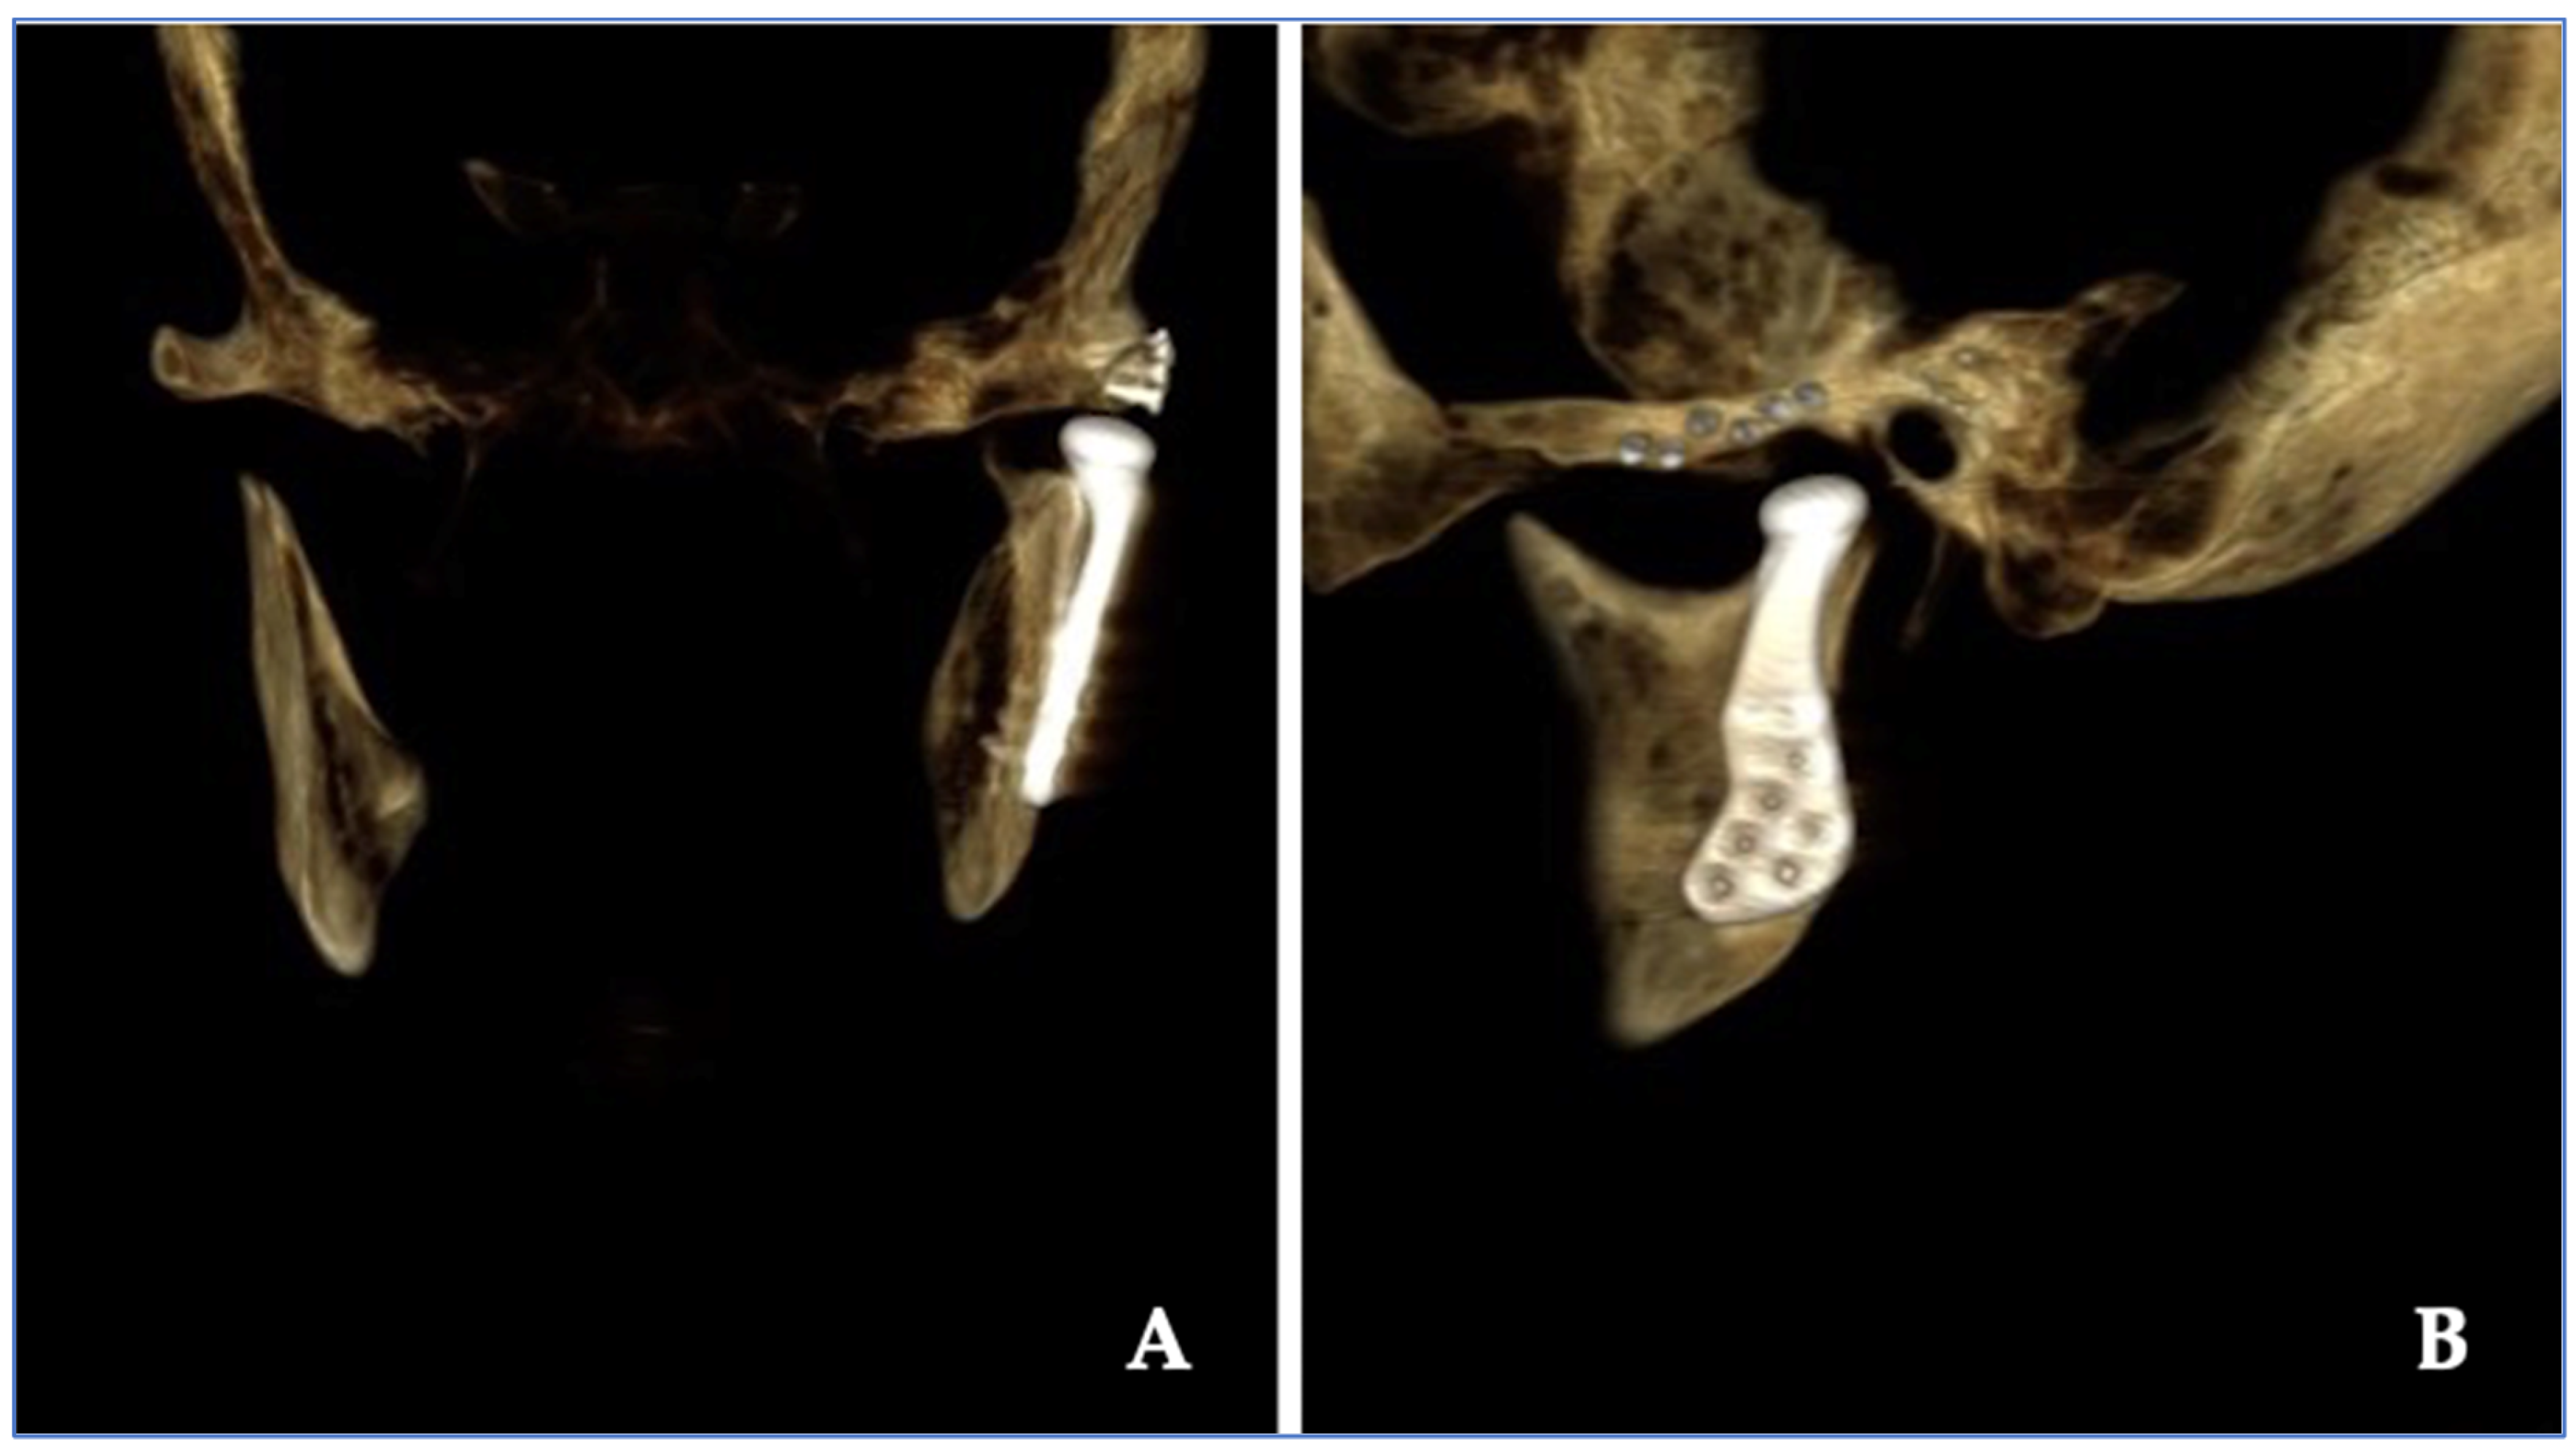

| 3 | 57/M | Posterior open bite | Bone destruction | 8 | 0 | 4.2 | 4.8 | Chondrosarcoma | Right |